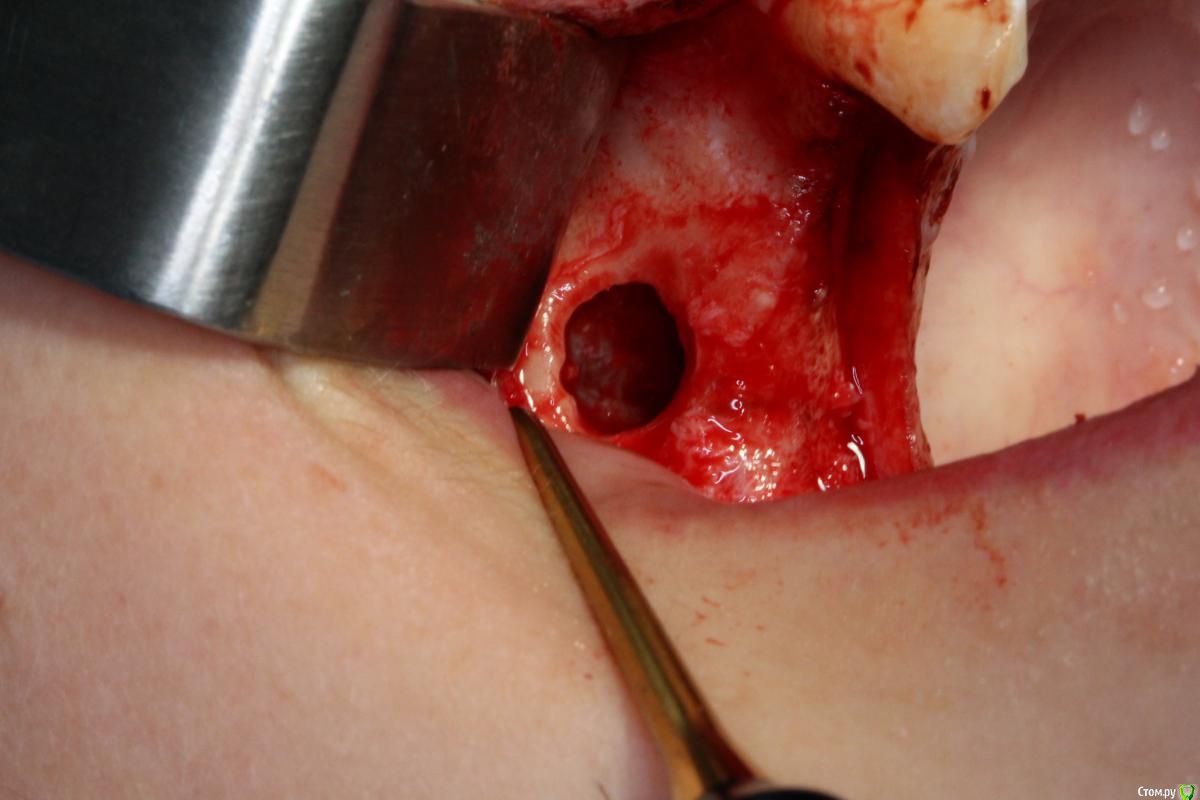

Robinbobin Опубликовано 25 марта, 2015 Поделиться Опубликовано 25 марта, 2015 Имплантаты Dio UF ll,костный материал ауто+остеоматрикс.Хотелось бы услышать мои ошибки 6 Ссылка на комментарий

Robinbobin Опубликовано 25 марта, 2015 Автор Поделиться Опубликовано 25 марта, 2015 я бы обошелся без вертикального разреза, и делал бы разрез по гребню. Почему делали открытый синус? Я делал разрез по гребню но из-за маленького опыта порвал((((Делал открытый потому что объем кости был 2-2.5 мм а боком поставить побоялся) Ссылка на комментарий

колесников Опубликовано 25 марта, 2015 Поделиться Опубликовано 25 марта, 2015 Вестибулярная компактная пластинка резорбируется на 3 мм у шеек имплантов. Вы конечно оставили дополнительно остеоматрикс вестибулярно ? В области 14 обязательно подсадите стт, можно на этапе формирователя. 16 можно было и короче взять,тогда бы он целиком находился в материале. А в целом Всё достойно. Ссылка на комментарий